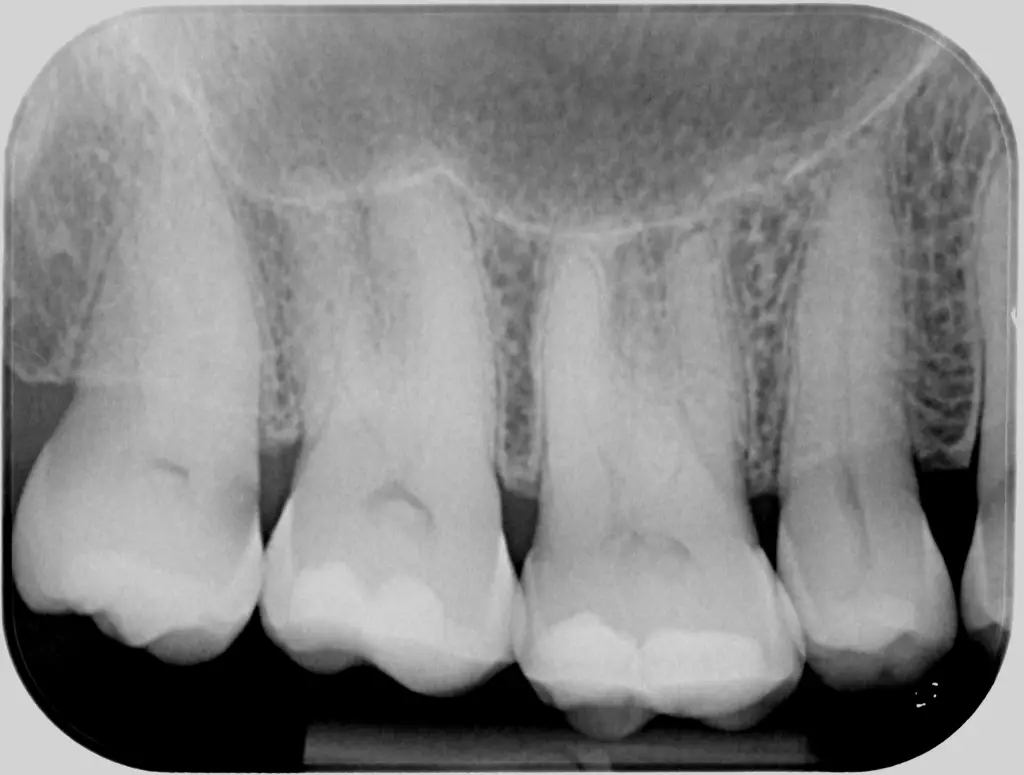

2. Periapikal røntgen (RTG)

• Formål

Denne type røntgen viser en hel tand og de nærmeste nabotænder, inddragende hele kronen og roden, samt det omkringliggende knoglevæv.

• Hvordan det tages

En film eller sensor placeres i munden tæt på tanden, og tandlægen tager et billede af den enkelte tand og dens rodstruktur.

• Hvornår det er indiceret

Periapikale røntgen bruges, når vi har behov for at vurdere tilstanden af tandrødderne inden en behandling eller ved mistanke om tandinfektioner og rodbehandlingsbehov.

Periapikalt røntgenbillede hos tandlægerne Ølandshus på Amager med fokus på kindtænder.